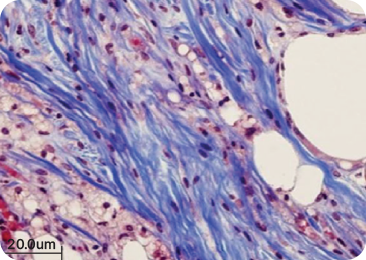

Tissue Regeneration Effect of HUCELLIN

hADM ECM의 조직 재생 효과

A. Control group : Saline injected

B. E1 group : ADM injected

C. E2 group : 1/2 volume of ADM

injected[comparing with B]

휴셀린 주입시 이종 콜라겐 제품과 비교하여

염증반응이 감소하고,

섬유조직 형성이 촉진되는 것을 확인함.